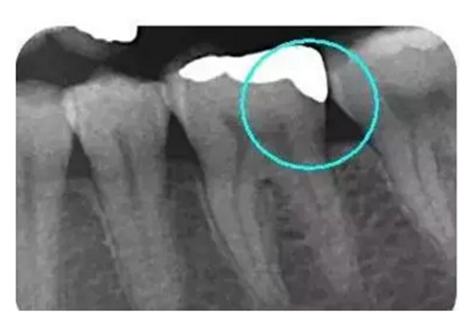

從下面這張X線中可以看出,嵌體遠(yuǎn)中邊緣沒有懸突,與牙體邊緣密合相接。